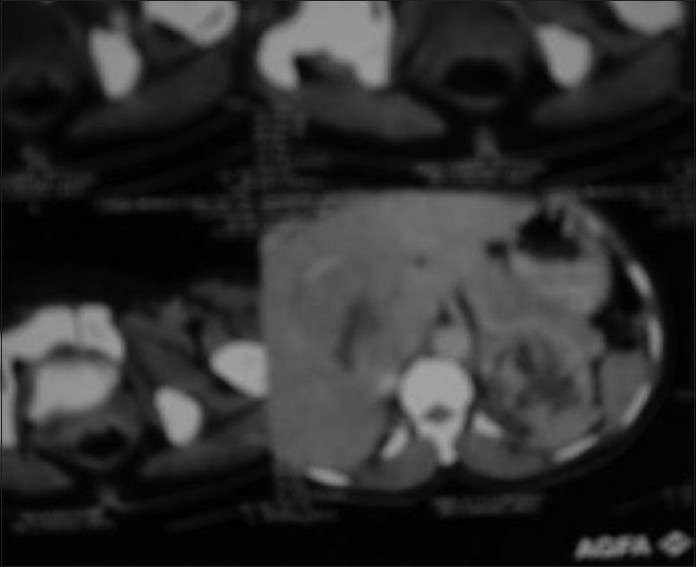

Skiagram of postero-anterior view of the chest revealed a fracture of the left clavicle [Figure 2]. Computerized tomography (CT) scan of the thorax was also advised, but the patient was unable to afford it. X-ray of the left limb showed a circumscribed lytic lesion in the lower shaft of the left femur. A whole-body bone scan (isotopic skeletal survey) with 99 m technetium-methylene diphosphonate revealed abnormally increased uptake over the left clavicle and distal end of left femur [Figure 3]. CT scan of the whole abdomen revealed multiple ill-defined hypodense enhancing space occupying lesions of varying sizes involving both lobes of the liver [Figure 4]. There was a 7.9 × 6.8 cm irregular heterogenous enhancing lesion of the left adrenal gland displacing the upper pole of the left kidney. The adrenal gland of the right side showed no abnormality. There was no retroperitoneal lymphadenopathy. ECG was within normal limits.

| Figure 4 Computerized tomography scan of abdomen showing a heterogeneous suprarenal mass on the left side and a heterogeneous space occupying lesion in the liver